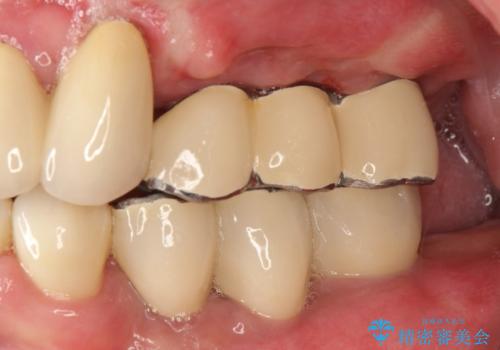

虫歯だらけ、歯周病 崩壊した口腔の再建 フルマウスリコンストラクション

費用・時間は多大にかかりましたが、今後しっかりと咬んで生活することができるでしょう。

かみ合わせの力が非常に強く、夜間の歯ぎしり・食いしばりもひどかったため、奥歯はメタルオクルーザルの設計でかぶせ物を製作しています。

かぶせ物の種類:PFZ / PFM metal occlusal